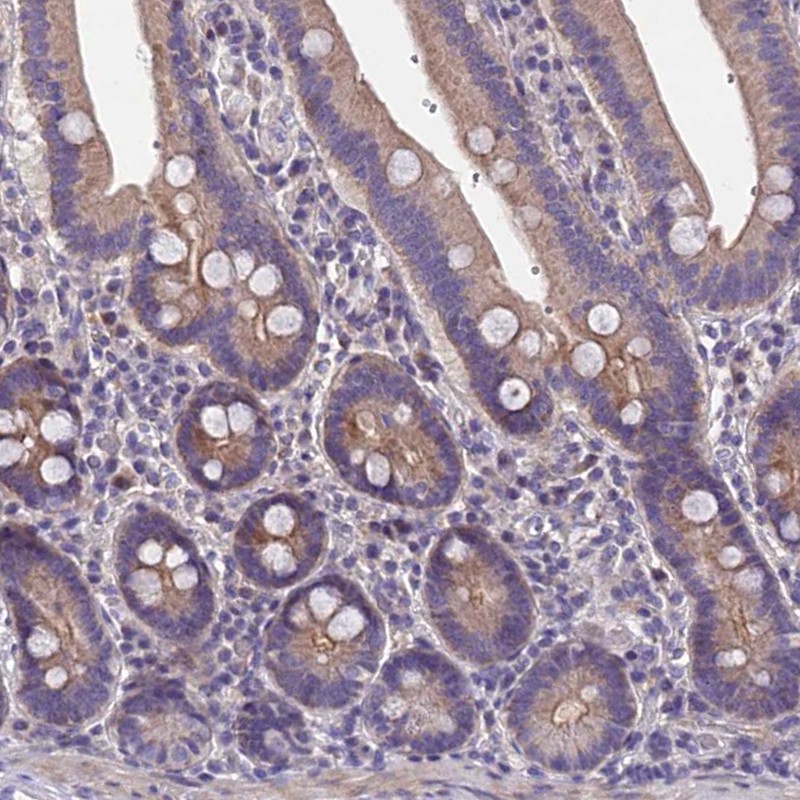

Immunohistochemical staining of human duodenum shows moderate cytoplasmic positivity in glandular cells.